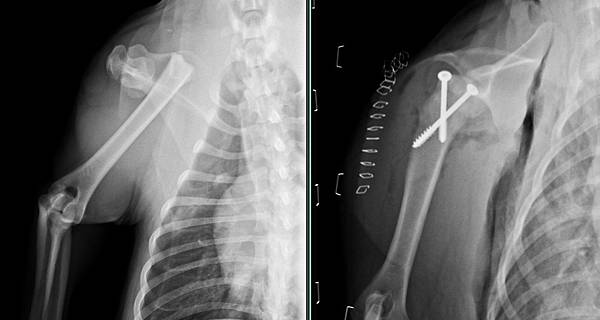

被車撞後前腳不敢著地

檢查發現手臂肱骨近端生長板骨折

經過醫療團隊努力

順利的完成手術